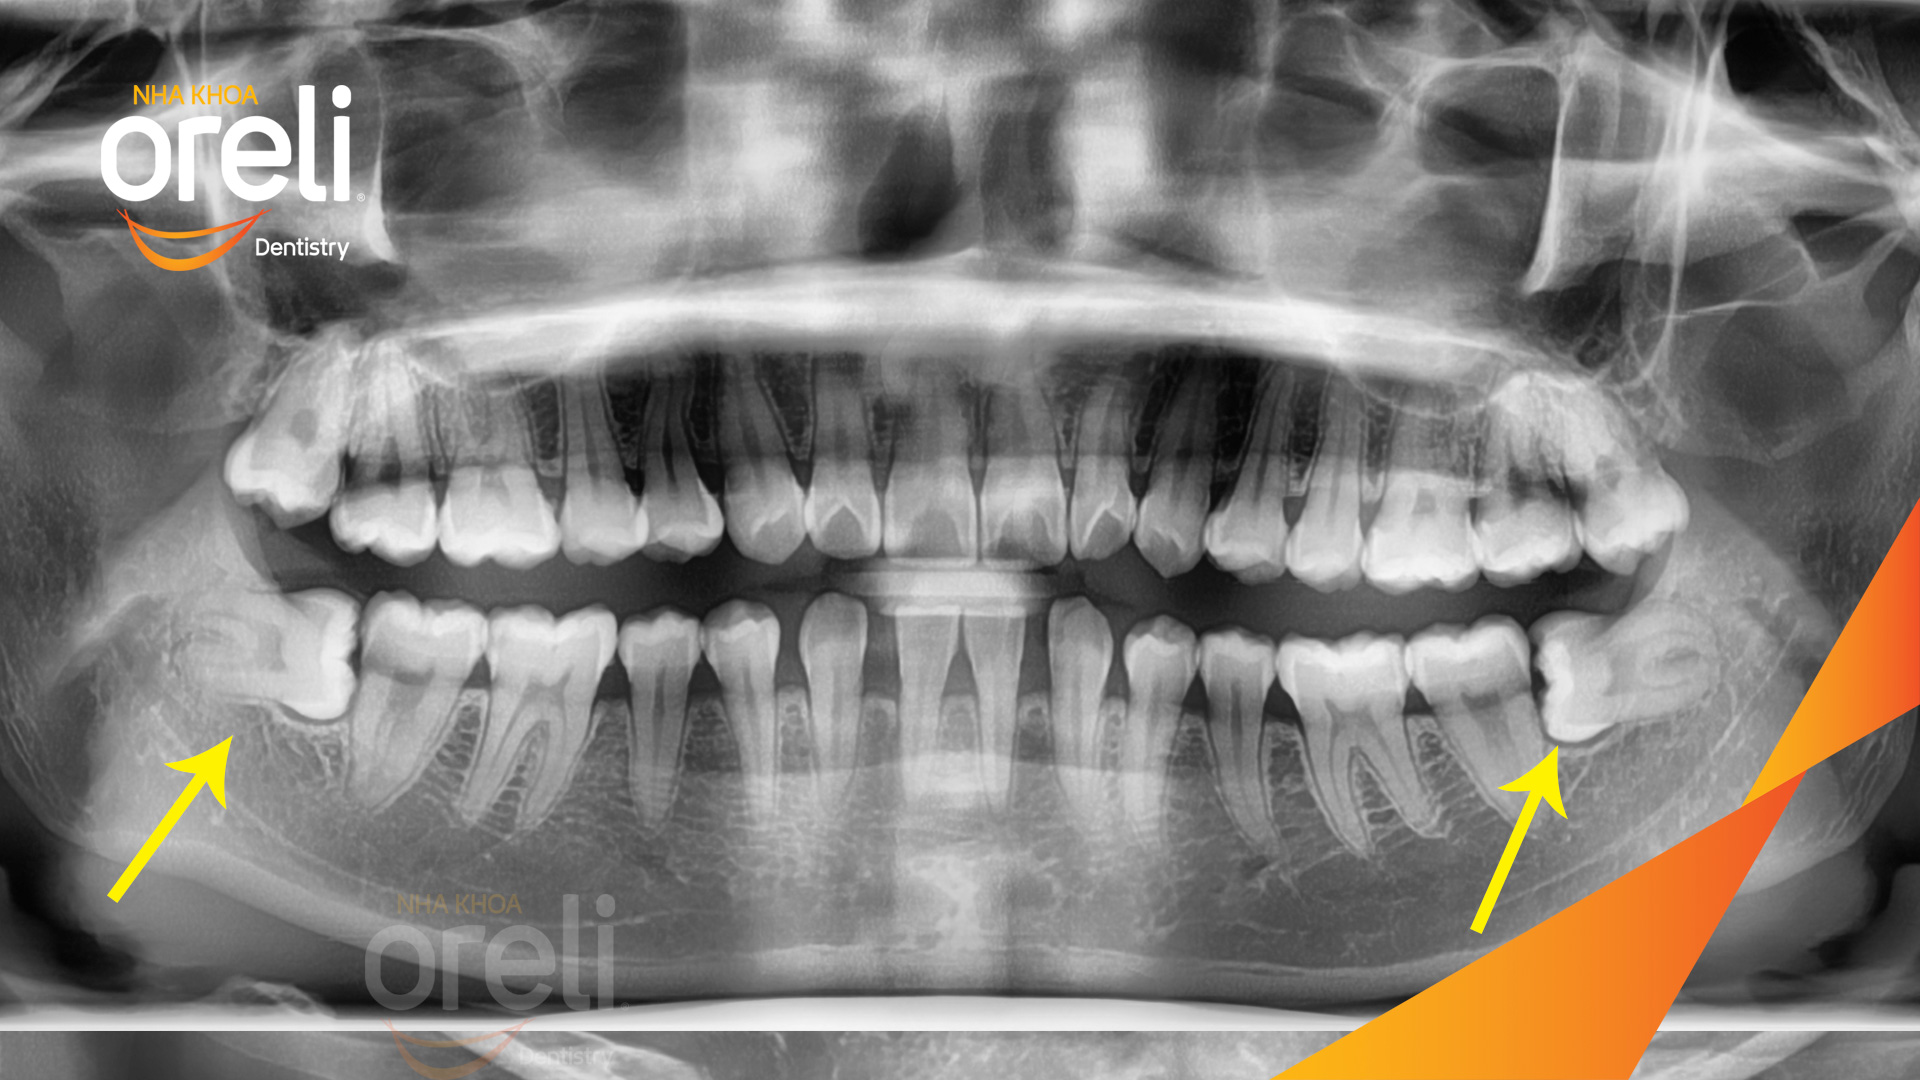

Ca nhổ răng khôn ảnh hưởng răng bên cạnh – Điều trị tại Oreli

Nhổ răng khôn

Mọc lệch

Xem thêm